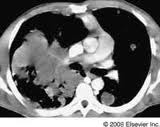

| Central bronchogenic carcinoma causing mediastinal invasion |